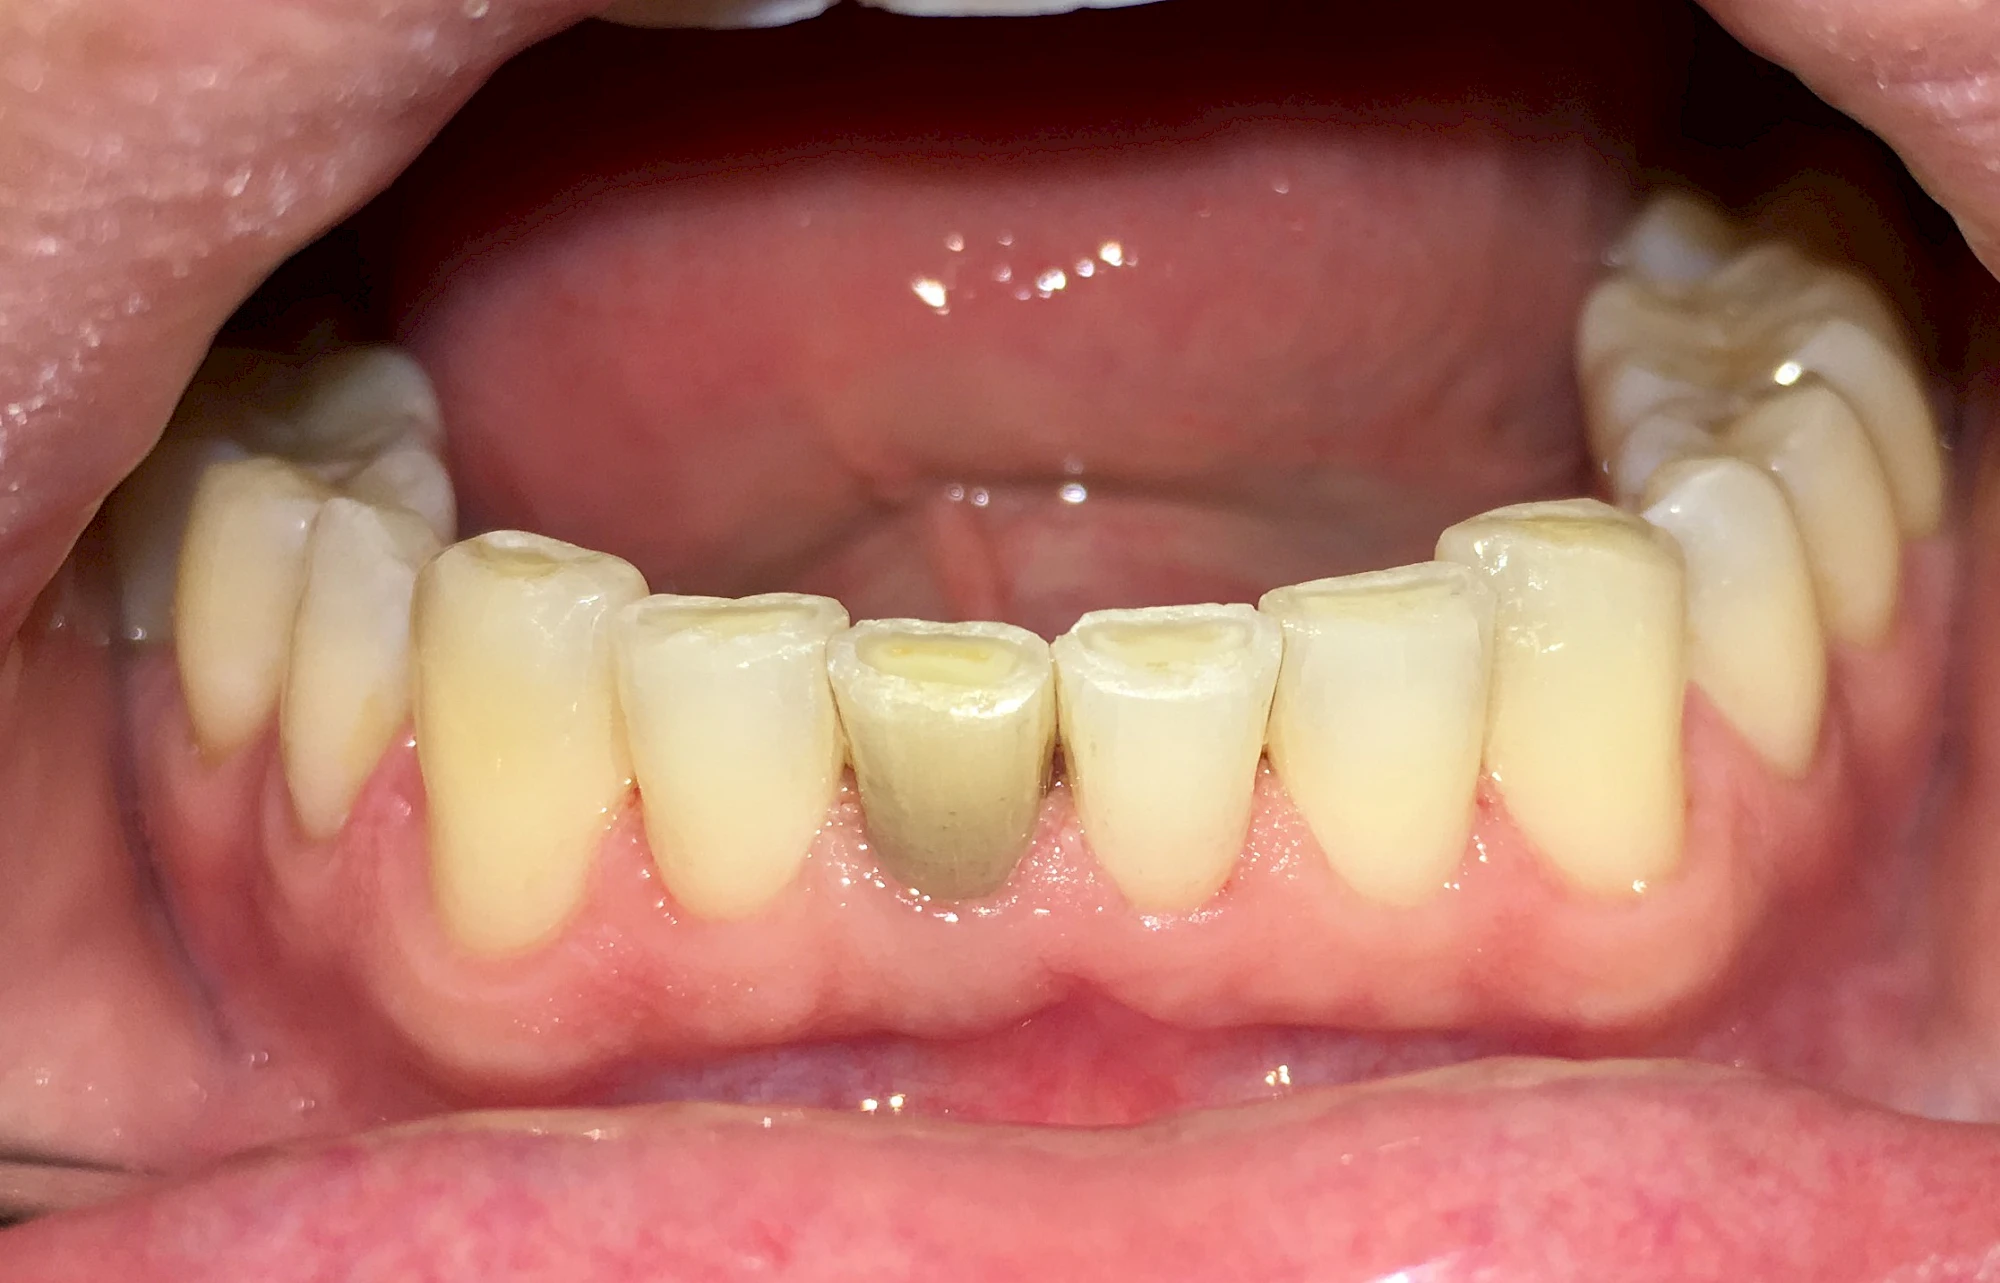

Von innen (endogen)

- Durch Blutabbauprodukte, weil der Zahnnerv abgestorben (einzelner Zahn, dunkel-flächig)

- Durch übermäßige Fluorideinlagerung in der Zahnreifung (mehrere Zähne, weißlich-fleckig)

- Durch Medikamente während der Zahnreifung (einzelne Zähne auf beiden Seiten, z. B. bläulich durch Antibiotikum Tetrazyklin)

Manche Medikamente wie zum Beispiel das Antibiotikum Tetrazyklin kann bei Einnahme im Zeitfenster der Zahnentwicklung auch irreversibel in die Zahnsubstanz. eingelagert werden. Tetrazyklin verfärbt die jeweils betroffenen Zähne bläulich und sollte deshalb während der Schwangerschaft und bei Kindern nicht verordnet werden.

Daneben gibt es noch seltene genetisch bedingte Schmelz- bzw. Dentinbildungsstörungen (Amelogenesis imperfecta, Dentinogenesis imperfecta), die neben Verfärbungen vor allem auch durch Veränderungen der Oberflächenstrukturen auffallen. In diesen Fällen ist eine engmaschige Betreuung durch den Zahnarzt wichtig.